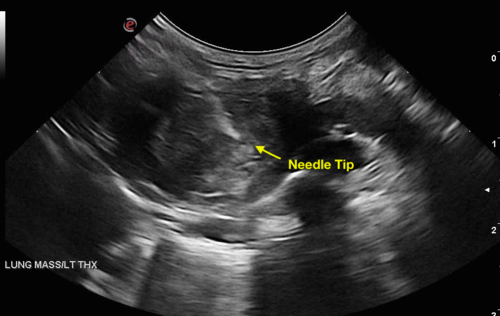

Mobile Imaging Veterinary Ultrasound (MiVU) is a mobile veterinary ultrasound service serving Richmond and the Hampton Roads area veterinarians.  MiVU conveniently offers advanced diagnostic ultrasound capability performed in your hospital thereby allowing you to preserve and maintain your doctor / client / patient relationship.  MiVU's goal is to provide services that are consistently prompt, accurate, and affordable. Services provided include but are not limited to abdominal ultrasound, echocardiogram with cardiologist interpretation, fine-needle biopsies, tru-cut biopsies, and cavity centesis.